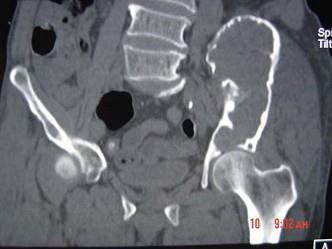

问题 患者,女性,68岁,近2年来感左髋部疼痛,活动后加重,2周前由于剧烈运动后左下肢活动不能,查体左髋部压痛明显,皮肤稍显红肿,请结合所提供的图像,选择最佳选项 ( )

选项 A、转移瘤 B、软骨肉瘤 C、骨巨细胞瘤 D、动脉瘤样骨囊肿 E、骨囊肿

答案 D